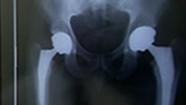

The system relies on x-ray imaging to help guide the placement of a rod into the femur, capped with a new artificial ball joint.

After implanting the ball and joint, Mast compares the placement to images taken before the procedure.

"We've got pretty good reproduction of the geometry of his hip," Mast said.